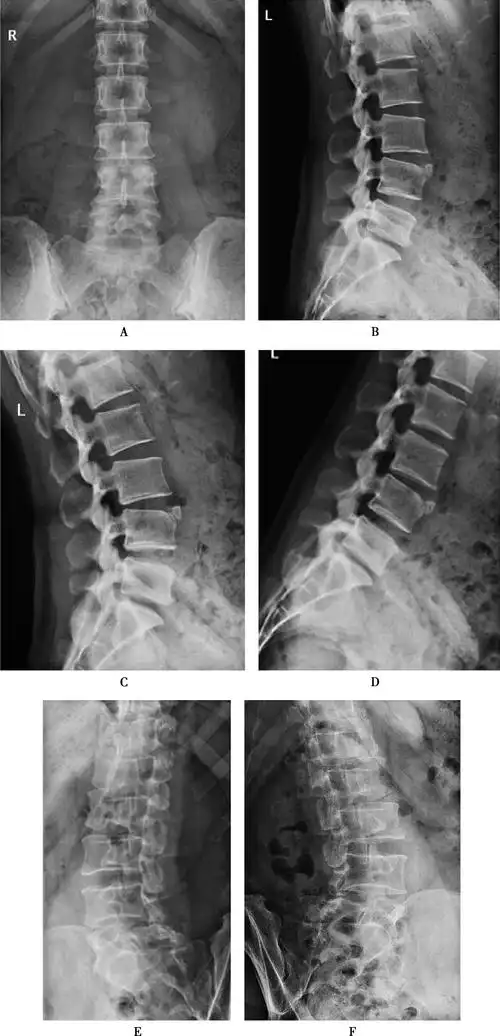

图4-1-3 腰椎dr